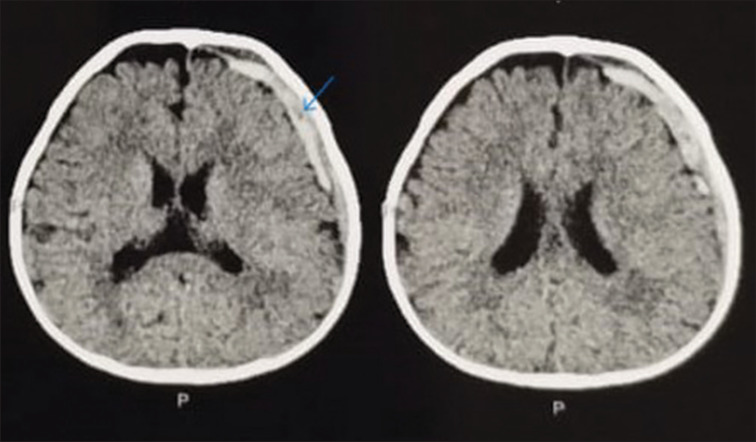

Acute subdural hematoma (ASDH) is a type of intracranial hemorrhage and is due to the collection of blood below the inner layer of the dura but external to the brain and arachnoid membrane. It tends to occur in the temporal parietal regions. Early intervention is the key for better outcome of the patient. Management depends on neurological status and imaging. Large SDH collects along the convexity of the brain causing compression over the brain stem with midline shift. In cases of conservatively managed ASDH, spontaneous resolution usually takes weeks to months depending on the size of the bleed. In rare cases, spontaneous rapid resolution of the SDH occurs. So here, we are presenting an 11-month-old baby girl who was brought to our Emergency room/department (ER) with a history of fall and computed tomography scan was suggestion of an ASDH in the left temporoparietal region which resolves on its own in 6 h which is a rare phenomenon and needs to be highlighted.